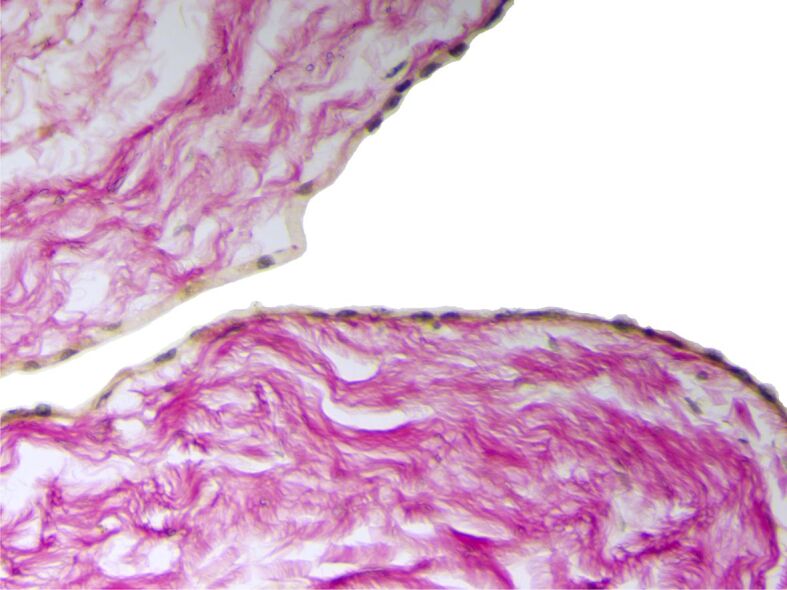

心包囊肿(PCs)或胸膜心包囊肿是一种罕见的先天性纵隔病变,发病率约为十万分之一。它们通常没有症状,是在常规胸部成像检查或尸检时偶然发现的。本研究对在罗马尼亚雅西肺病诊所接受治疗的 6 年系列 PCs 的临床病理结果进行了回顾性评估。共评估了五例肺结核患者,其中四例为女性,一例为男性。所有患者均表现出不同的症状,如呼吸困难、胸痛、慢性咳嗽、疲劳、心悸和上腹痛。四例患者的囊性病变位于左右心膈角,一例患者的囊性病变位于中央纵隔。病灶中含有液体,最大直径在 35 至 95 毫米之间。手术切除组织的显微镜检查显示,结缔组织壁很薄,没有任何相关的平滑肌细胞。疏松的结缔组织带内衬一层无细胞不典型性的间皮细胞,其中一例显示出离散的乳头状突起。虽然 PCs 是罕见的偶然发现,但在纵隔囊肿的鉴别诊断中应考虑到它们,尤其是当它们与非特异性症状相关时。此外,考虑到PC可能会引发严重的并发症,因此应彻底检查PC,以便对患者进行适当的治疗。

Pericardial cysts (PCs) or pleuropericardial cysts are rare congenital mediastinal lesions with an approximate incidence of one in 100 000 persons. Usually, they are asymptomatic, being incidentally discovered during a routine chest imaging examination or an autopsy exam. The study involved a retrospective evaluation of clinicopathological findings in a 6-year series of PCs, treated in the Clinic of Pulmonary Diseases, Iaşi, Romania. A group of five cases of PCs, four females and one male, were evaluated. All patients displayed different symptoms, such as dyspnea, chest pain, chronic cough, fatigue, palpitation, and epigastric pain. The cystic lesions were located in the right and left cardiophrenic angle, in four cases, and in the central mediastinum in a single case. The lesions had a fluid content and a maximum diameter that ranged between 35 and 95 mm. The microscopic examination of the surgical resection tissues revealed a thin connective tissue wall without any associated smooth muscle cells. The loose connective tissue band was lined by a layer of mesothelial cells with no cellular atypia, which displayed discrete papillary projections, in one case. Although PCs are rare incidental findings, they should be considered in differential diagnoses of mediastinal cysts, especially as they are associated with non-specific symptoms. Furthermore, considering the possibility of development of severe complications, PCs should be thoroughly explored for suitable patients' management.